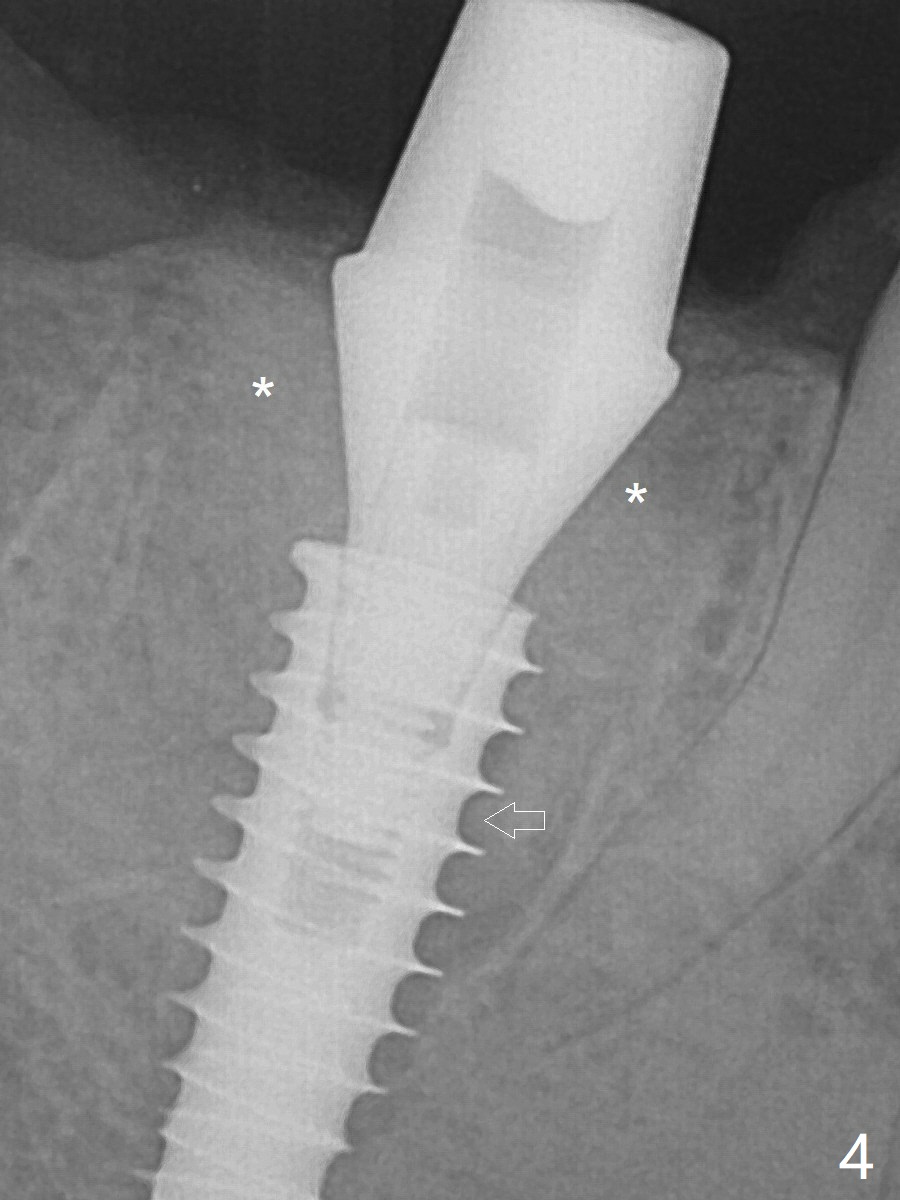

The definitive IBS implant (5x13 mm) is placed with 50 Ncm; a 6.5x5.7(4) mm abutment is placed with allograft filling the gap (Fig.4 * and arrow).